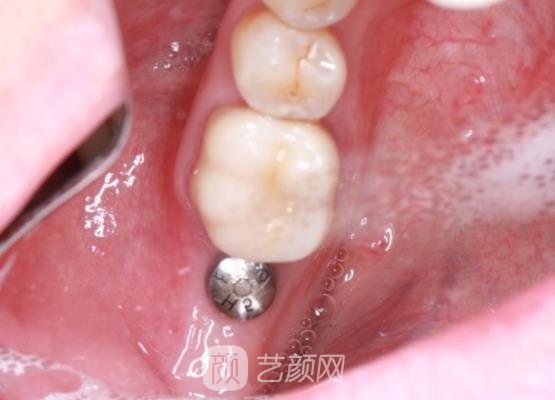

方案制定好之后就开始了手术,刚开始时我也是比较害怕的,不过可能是因为有麻药的加持,我也没有感觉到什么剧烈的疼痛感,所以后来我也就没有那么的害怕了,手术几个小时就结束了,没有浪费我很多的时间。

刚结束手术的时候,我的牙龈处存在着一些肿胀的情况,还有一些疼痛的感觉,这让我比较担心,询问了医生以后,医生告诉我这些现场比较正常,然后给我开了一些消炎药让我定时服用,果然吃了消炎药以后,我牙龈的状况好了很多。